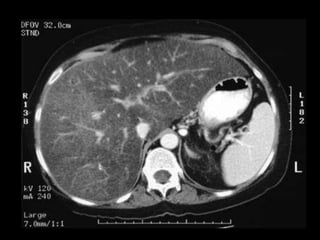

• LA TOMOGRAFIA TIENE EL MAYOR EFECTO.

• DETECCION EXELENTE PARA PACIENTES

POLITRAUMATIZADOS HEMODINAMICAMENTE

ESTABLE

• VALORACIÒN INICIAL.

• VER LOCALZACIÒN Y EXTENSIÒN

• EN TC :

CONTUSION SIN ROTURA SE MANIFIESTA COMO

IMAGEN HIPODENSA EN CONTRASTADA ESTO

PUEDE SER POR EDEMAS Y HEMORRAGIAS

MICROSCÒPICAS